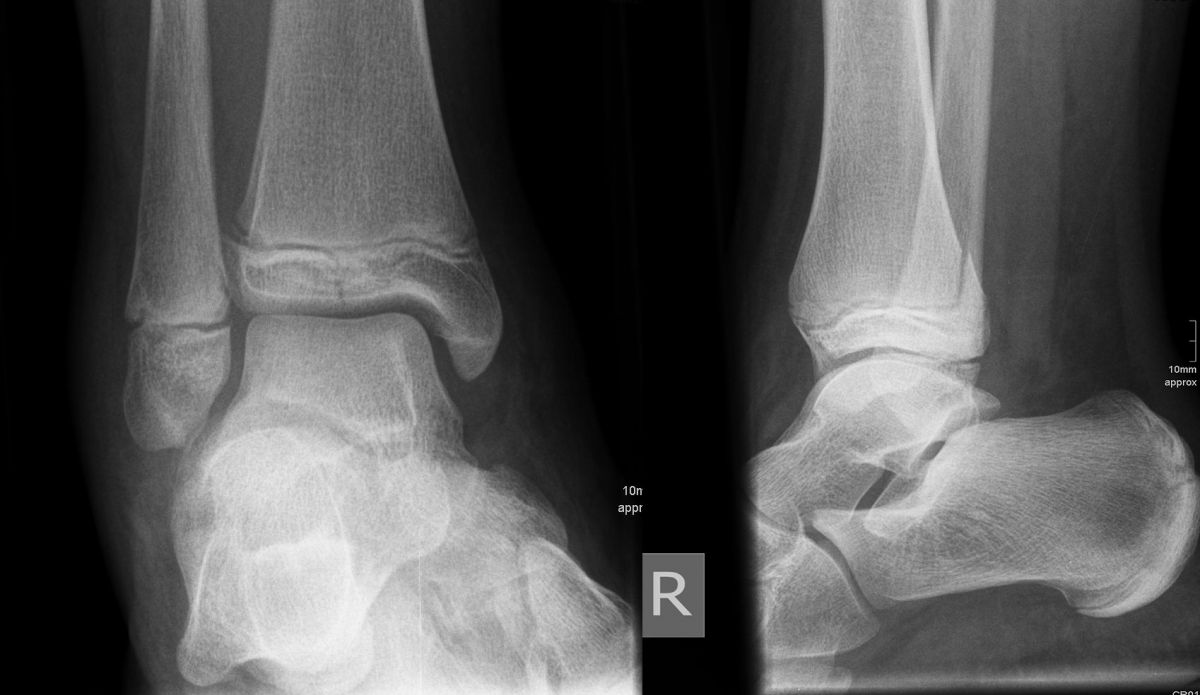

Bei den medialen Malleolarfrakturen handelt es sich um Fugengelenkfrakturen bzw. Aitken II und III Verletzungen. Kennzeichnend ist, dass der Frakturverlauf die wachstumsaktive Zone zur Epiphyse hin durchkreuzt. Die Verletzung der wachstumsaktiven Zone macht diese Verletzungen besonders problematisch.

Fugengelenkfrakturen treten typischerweise vor dem 10. Lebensjahr auf, in einer Phase, in welcher die Wachstumsfugen noch weit offen sind. Dieser Frakturtyp betrifft fast ausschließlich den medialen Malleolus. Laterale Frakturen sind extrem selten, teilweise kommt es zu lateralen Bandverletzungen oder Fugenschaftfrakturen der distalen Fibula. Die Frakturlinie verläuft in einer Verlängerungslinie von der medialen Taluskante nach proximal. Häufig stellen sich Verletzungen des Innenknöchels im Röntgenbild schlechter dar, insbesondere wenn die Aufnahmen verdreht sind oder die Ebene der Fraktur bei geringer Dislokation verkippt zur Röntgenebene liegt. Besteht klinisch der geringste Hinweis auf eine Verletzung des Innenknöchels, muss aufgrund der Tragweite der Verletzung durch entsprechende Aufnahmen gegebenenfalls auch Schnittbildverfahren die Verletzung sicher diagnostiziert oder ausgeschlossen werden (Abb. 15).

Bei kindlichen Verletzungen des medialen Malleolus handelt es sich nach L. v. Laer um eine sogenannte Kadiläsion, d.h. eine Verletzung mit hohem Risiko eines schlechten Behandlungsergebnisses bei nicht korrekter Behandlung. Selbst bei optimaler Therapie ist das Risiko für spätere Wachstumsstörungen hoch, sodass diese Verletzungen nicht selten ein juristisches Nachspiel haben. Durch die Verletzung der wachstumsaktiven Zone kann es zu einem vorzeitigen Verschluss der Wachstumsfuge kommen, mit entsprechendem Fehlwachstum. Das Risiko eines vorzeitigen Verschlusses der Wachstumsfuge korreliert mit dem Ausmaß der Schädigung der wachstumsaktiven Zone. Ab dem 13. Lebensjahr wird das Risiko bei reduzierter Wachstumsaktivität zunehmend geringer.

Fugengelenkfrakturen können die Wachstumsfuge durchkreuzen (Abbildung 16a), ohne oder nur mit minimaler Beteiligung der Fuge sehr weit medial liegen (Abbildung 16b) oder durch die Fuge auslaufen (Abbildung 16c). Relevant für die Wachstumsprognose ist weniger die Form der Fraktur, sondern das Alter des Patienten zum Zeitpunkt des Traumas sowie das Ausmaß der Schädigung der Wachstumsfuge, wobei eine Korrelation mit dem Ausmaß der Dislokation besteht.